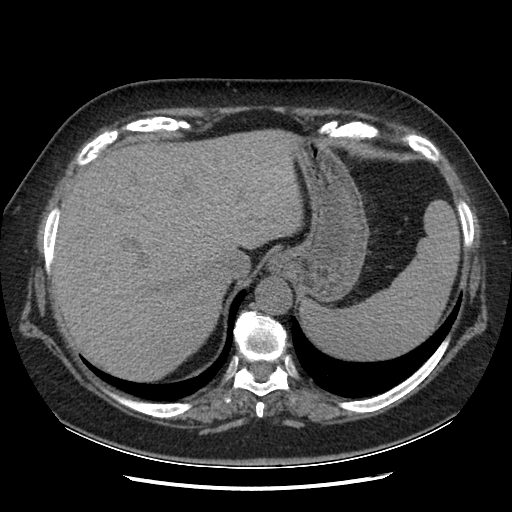

Original NATIVE CT scan (input)

Full window (WL 1023.5, WW 4095 → Low −1024, High +3071)

Actual HU range: [-160.0, 240.0]